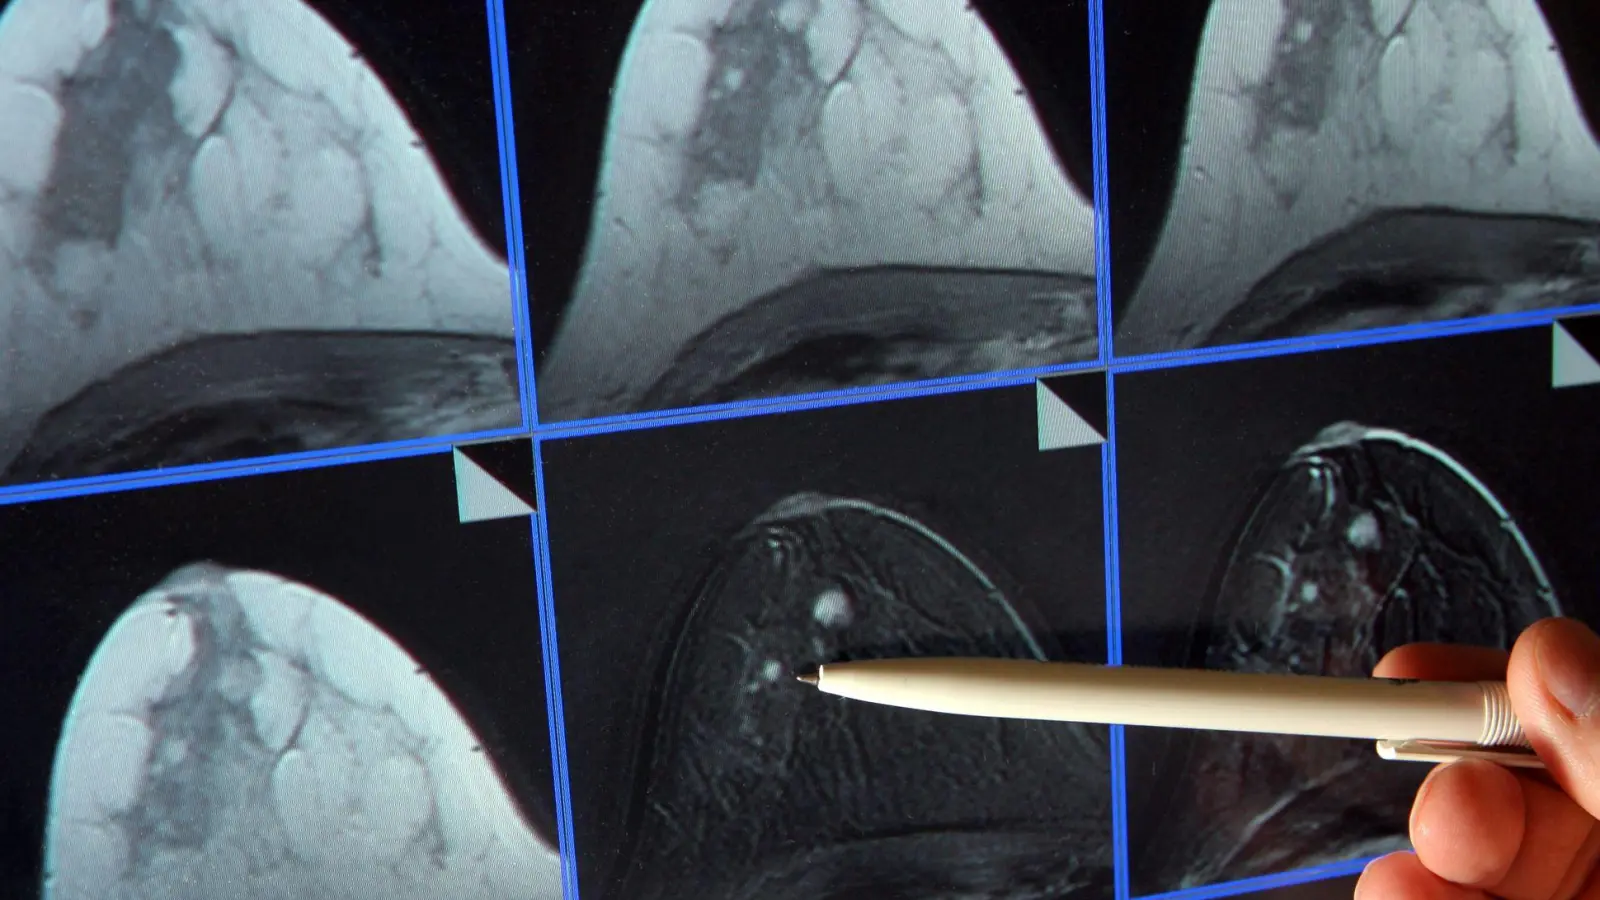

Im Zuge des Mammographie-Screening-Programms können Frauen alle zwei Jahre eine Röntgen-Untersuchung der Brust zur Früherkennung in Anspruch nehmen. (Archivbild) (Foto: Jan-Peter Kasper/dpa-Zentralbild/dpa)

Kuhl ist überzeugt, dass sich die Zahl der an Brustkrebs sterbenden Frauen stark senken ließe. Dazu müsse die Früherkennung besser individuell angepasst werden. So sollten etwa Frauen mit sehr dichtem Brustgewebe, bei denen eine Mammografie nicht ausreicht, alternative Früherkennungsverfahren angeboten werden – insbesondere die Magnetresonanztomographie (MRT), für die es die höchste wissenschaftliche Evidenz gebe. Dieses Verfahren liefere umso bessere Nachweise, je aggressiver ein Karzinom sei.

MRT - bei vielen Frauen die weitaus bessere Wahl?

Etwa zehn Prozent der Frauen haben ein extrem dichtes Brustgewebe. Sie würden durch das derzeitige Mammografie-Screening unterversorgt, heißt es auch von der Europäischen Gesellschaft für Brustbildgebung (EUSOBI). Es gebe Nachweise, dass MRT-Untersuchungen die Brustkrebs-Sterblichkeit bei ihnen erheblich senken könne. Frauen sollten von ihren Ärzten generell über ihre Brustdichte informiert werden. Die Fachgesellschaft empfiehlt, Frauen im Alter von 50 bis 70 Jahren mit extrem dichter Brust alle zwei bis vier Jahre ein MRT-Screening anzubieten.

In Deutschland müssen Frauen in diesen Fällen MRT-Untersuchungen selbst zahlen. Die gesetzlichen Krankenkassen übernehmen die etwa 350 Euro für eine Früherkennungs-MRT nur bei einem nachweislich deutlich erhöhten Risiko für Brustkrebs – etwa bei einer BRCA1- oder BRCA2-Genmutation oder familiärer Belastung. „Auch wenn Mammografie und Ultraschall keine eindeutigen Ergebnisse liefern, kann ein MRT zur weiteren Abklärung von unklaren Befunden eingesetzt werden“, erklärte Kolberg.